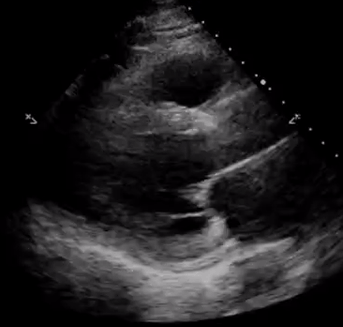

PLAX severe Leave a ReplyCancel reply Search for... Search NephroPOCUS video curriculumPOCUN pearls = short videosMy POCUS posts on the Renal Fellow Network https://www.renalfellow.org/tag/abhilash-koratala/ Sign up for NephroPOCUS updates Enter your email address to receive notifications of new posts. Email Address Subscribe Follow me on twitterMy TweetsPOCUS video curriculum for Nephrology traineesFollow Me X My POCUS posts on the Renal Fellow Network POCUS gallery on the Renal Fellow Network Renal ultrasound review article ASN Kidey News article about POCUS Short videos – ‘POCUN pearls’ Tweets by NephroP